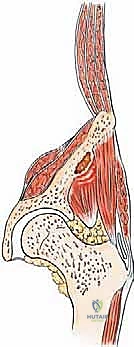

لفهم مدى تعقيد جراحة أورام الحوض، يجب أولاً إدراك العبء البيوميكانيكي الهائل الذي يتحمله هذا الجزء من الجسم. الحوض ليس مجرد مجموعة من العظام، بل هو "حلقة الوصل" الحيوية التي تنقل وزن النصف العلوي من الجسم (الرأس، الجذع، والذراعين) إلى الأطراف السفلية (الساقين) أثناء الوقوف والمشي. كما أنه يمثل درعاً واقياً للأعضاء الحيوية في أسفل البطن (المثانة، المستقيم، والأعضاء التناسلية) ونقطة ارتكاز لعشرات العضلات والأربطة القوية.

يتكون الحوض العظمي من اندماج ثلاثة عظام رئيسية في كل جانب، تلتقي جميعها لتكوين تجويف مفصل الورك:

- العظم الحرقفي (Ilium - الإليوم): هو الجزء العلوي العريض والمفلطح الذي يشكل أجنحة الحوض (الخواصر). يُعد موقعاً شائعاً جداً للانتشار السرطاني بسبب حجمه الكبير واحتوائه على كمية كبيرة من نخاع العظم.

- العظم الوركي (Ischium - الإسك): الجزء السفلي والخلفي من الحوض، وهو العظم الذي نرتكز عليه أثناء الجلوس. الأورام هنا تسبب آلاماً مبرحة عند الجلوس.

- عظم العانة (Pubis - الكيوبس): الجزء الأمامي السفلي الذي يربط نصفي الحوض من الأمام عبر الارتفاق العاني.

- الحُق (Acetabulum - الأستابولوم): هو التجويف نصف الكروي العميق الذي يتشكل من التقاء العظام الثلاثة السابقة. يستقبل هذا التجويف رأس عظم الفخذ ليشكلا معاً مفصل الورك. هذا الجزء هو الأهم ميكانيكياً، وأي تدمير سرطاني فيه يؤدي إلى عجز فوري عن المشي.